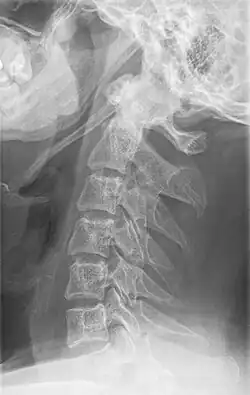

Radiograph, lateral view showing elongated stylohyoid process and stylohyoid ligament ossification -